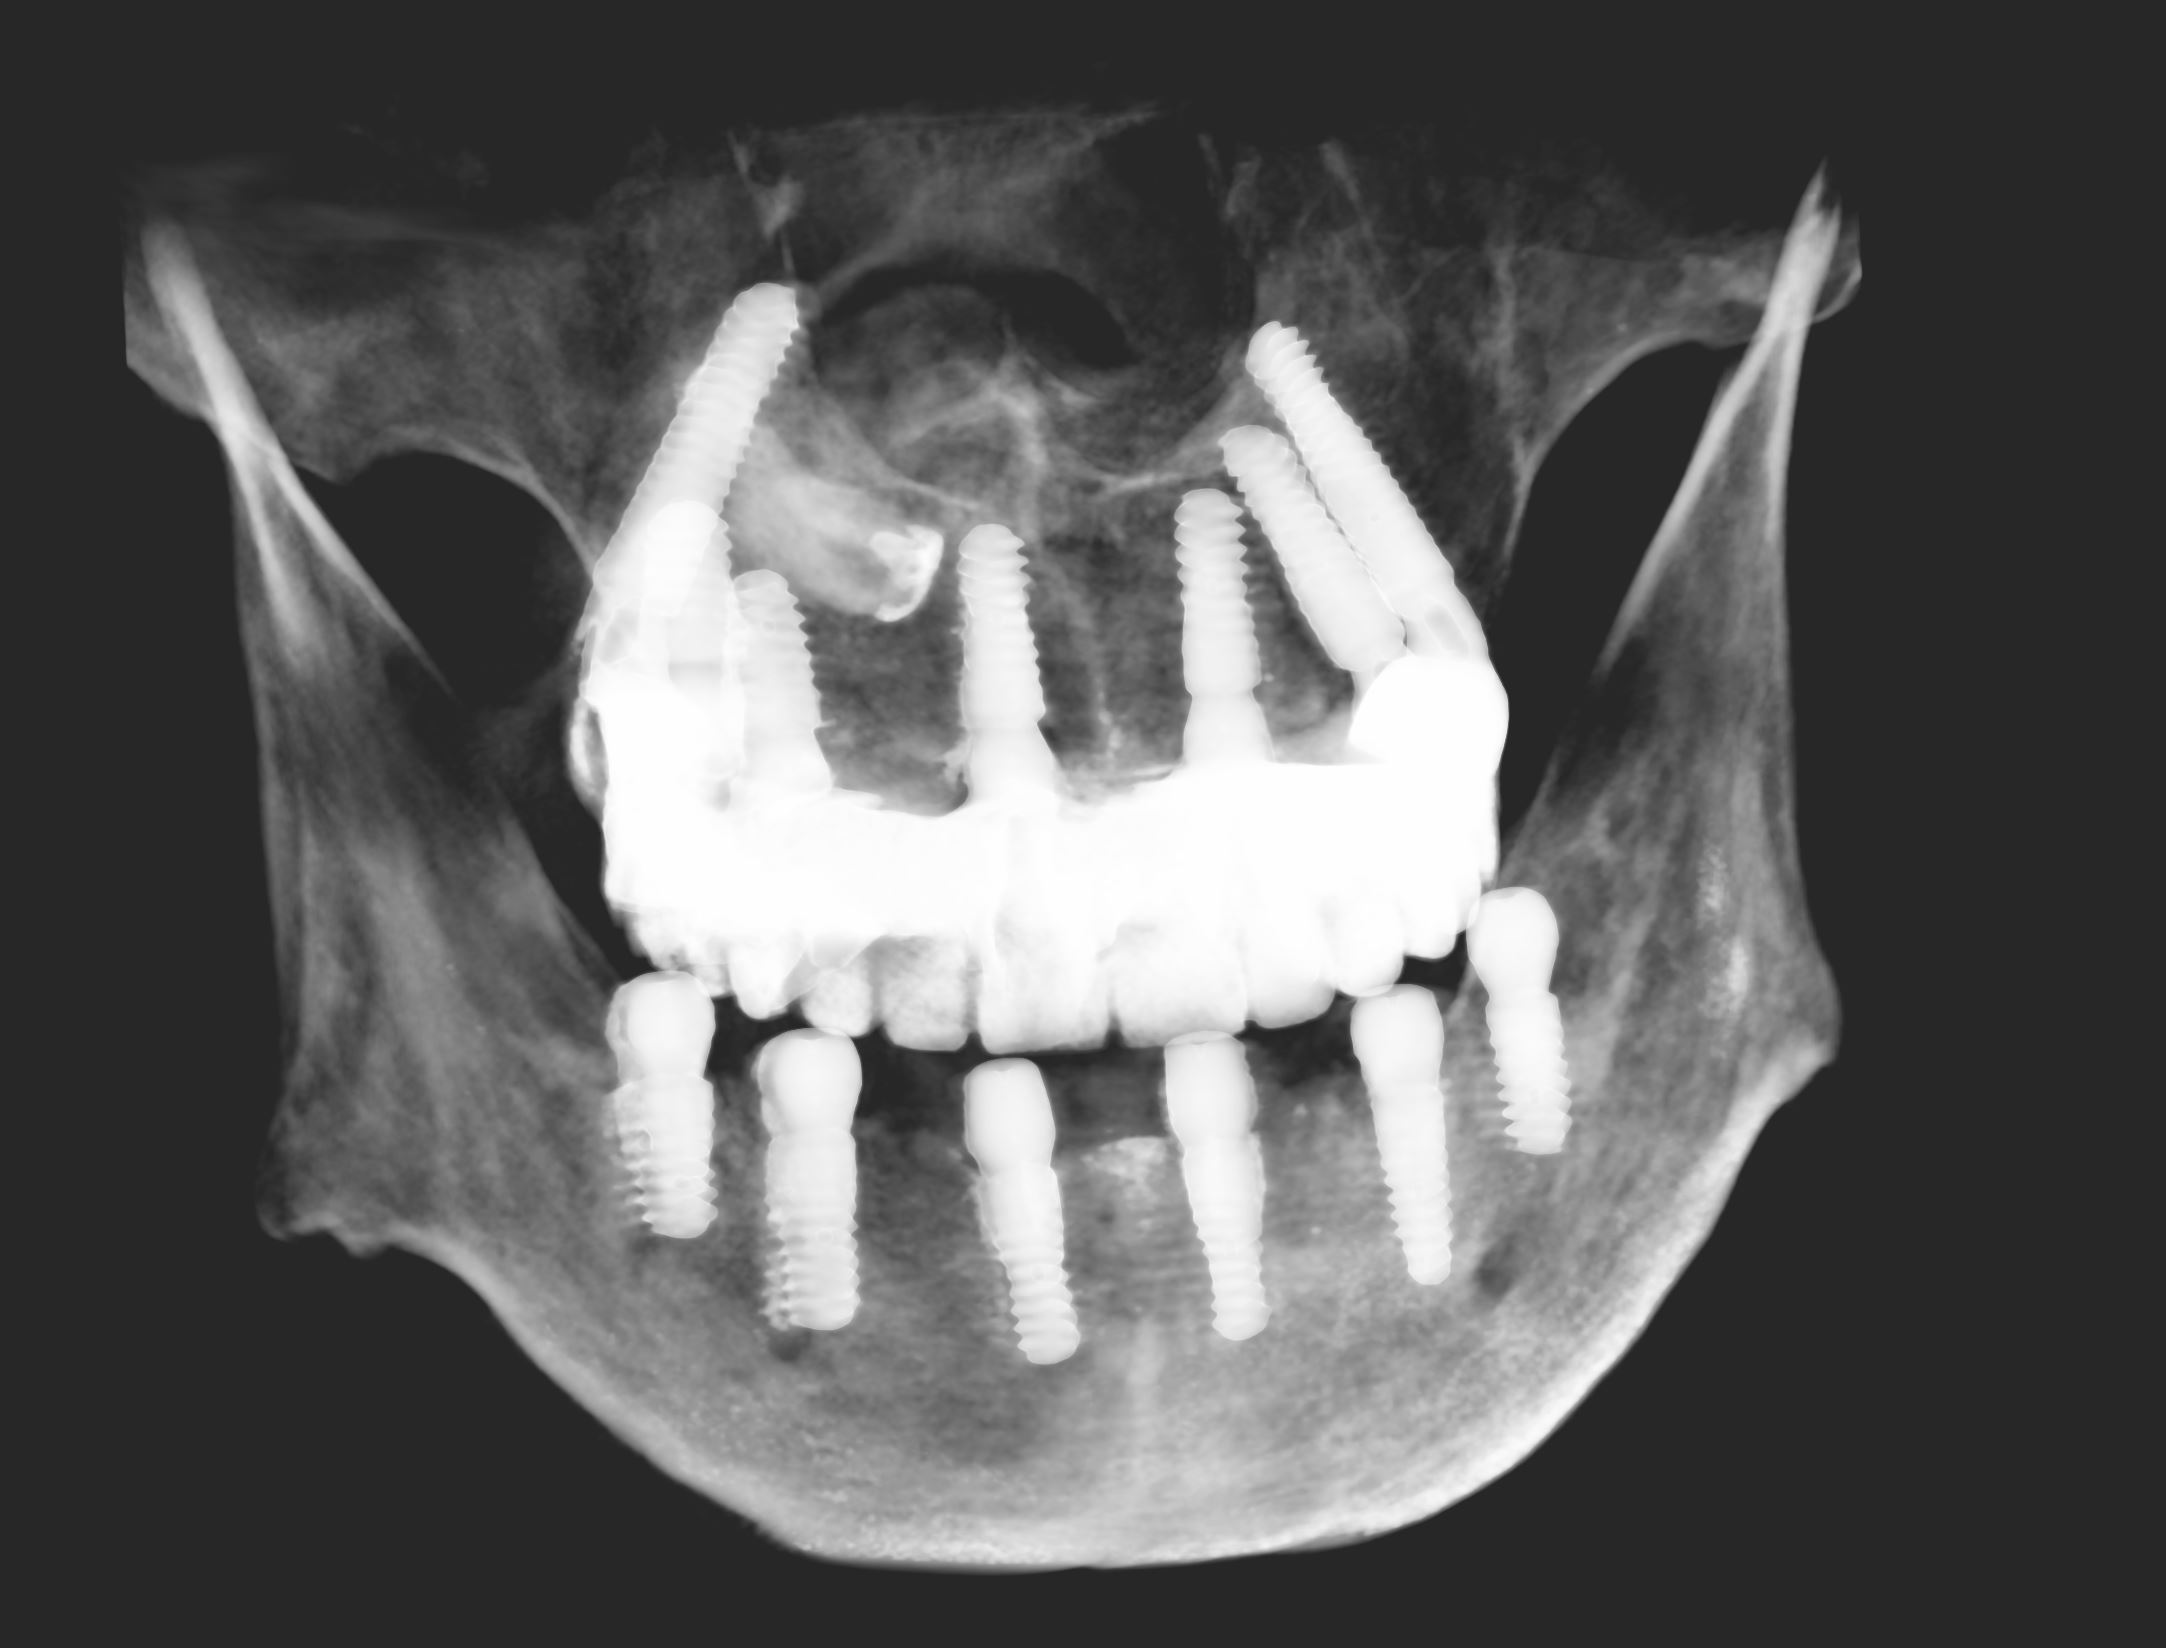

CZAR-DENT w Białymstoku odbyło się trzydniowe szkolenie poświęcone tej metodzie, podczas którego zrealizowano zabieg pełnołukowej rekonstrukcji uśmiechu w szczęce i żuchwie. Wszczepiono łącznie 13 implantów, które stanowiły podstawę do dalszego etapu odbudowy protetycznej.